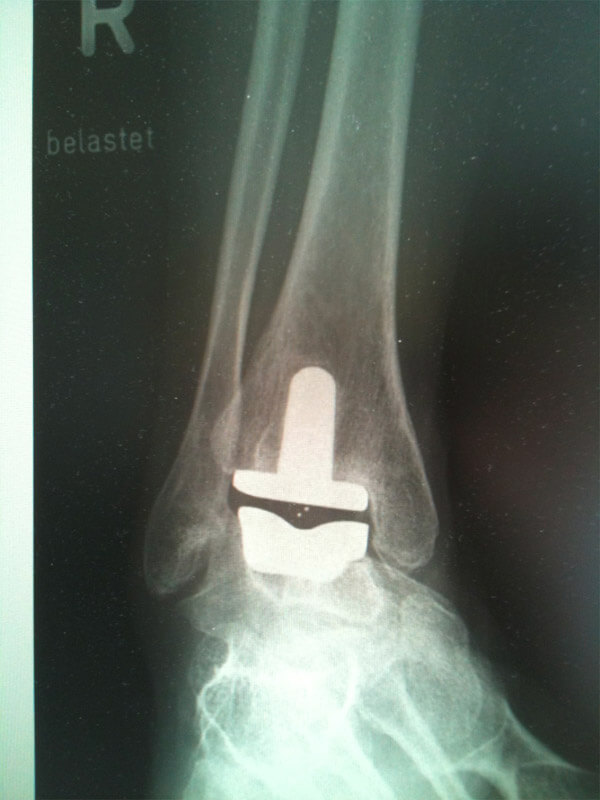

Αρθροπλαστική Ποδοκνημικής

Ενδείξεις

- Ρευματοειδής Αρθρίτιδα

- Οστεοαρθρίτιδα

- Αρθρίτιδα μετά από έναν τραυματισμό

- Σοβαρός Πόνος αστράγαλο

- Μια Προηγούμενη αρθρόδεση ποδοκνημικής

- Revision αρθροπλαστικής ποδοκνημικής

Πώς λειτουργεί η πρόθεση;

Η επέμβαση περιλαμβάνει την αντικατάσταση των φυσικών επιφανειών της άρθρωσης του αστραγάλου που έχουν εκφυλιστεί με τεχνητή κάλυψη γνωστή ως πρόθεση.

Η αρθροπλαστική ποδοκνημικής έχει τρία μέρη.

Δύο από τις συνιστώσες καλύπτουν τα οστά και στη μέση υπάρχει και ένα τρίτο, το κινητό στοιχείο (πολυαιθυλένιο).

Αυτό επιτρέπει μεγαλύτερη κίνηση και μειώνει την τριβή μεταξύ των οστών και των εμφυτευμάτων.

Όλα τα μεταλλικά στοιχεία καλύπτονται από μία βιοενεργή επίστρωση η οποία ενθαρρύνει την ενσωμάτωση στα οστά.

Αυτός ο τύπος λειτουργίας επιτρέπει στον ασθενή να διατηρήσει την κίνηση που έχει και να κερδίσει μερικούς βαθμούς ελευθερίας.